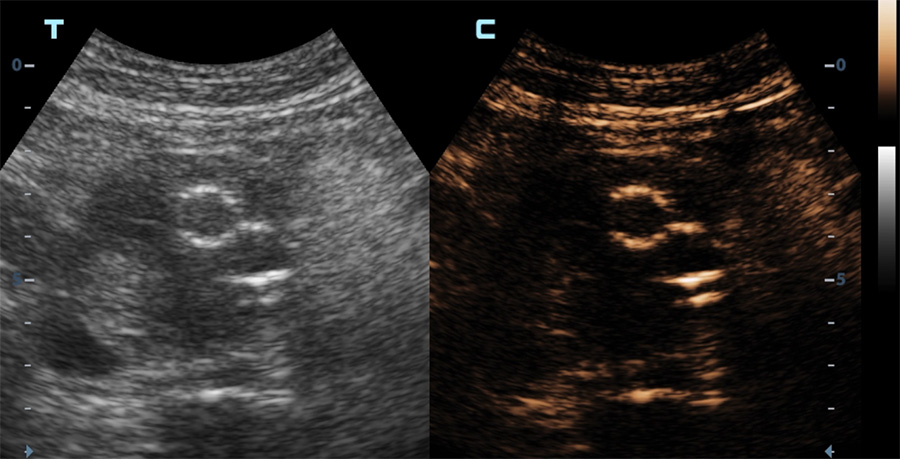

Echographie en mode contraste d’une endoprothèse aortique

Apparition du produit de contraste dans la lumière des vaisseaux